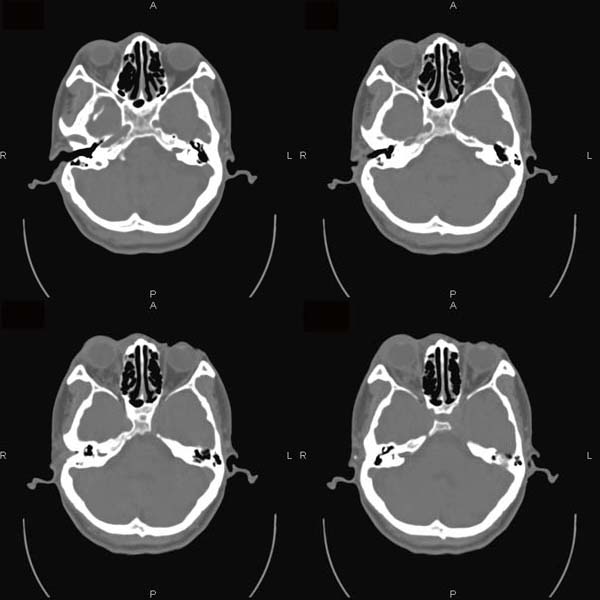

以下是引用逸风在2006-6-5 17:45:00的发言:[br]ct显示:右侧眼球轻度突出,眼环增厚,球后脂肪间隙模糊,可见点状高密度灶,同侧视神经稍增粗,周围眶壁骨质未见明显异常,眼环完整,球内未见明显异常密度.[br]诊断意见:1.右侧眼球钝挫伤合并球后间隙出血可能;2.右侧视神经挫伤待排.[br]建议必要时hrct扫描,排外其它.

以下是引用jiangjing在2006-6-5 23:41:00的发言:[br][图像处理较差]ct显示:右侧眼球轻度突出,眼环增厚,球后脂肪间隙模糊,可见点状高密度灶,同侧视神经稍增粗,周围眶壁骨质未见明显异常,眼环完整,球内未见明显异常密度.[br]诊断意见:1.右侧眼球钝挫伤合并球后间隙出血可能;2.右侧视神经挫伤待排.[br]建议必要时hrct扫描,排外其它